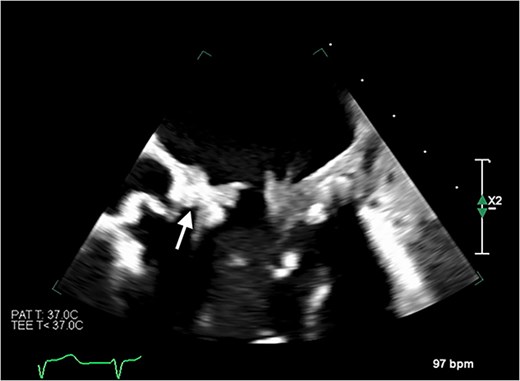

Despite initially recovering well postoperatively, she decompensated on postoperative day 5. Blood cultures and 16S polymerase chain reaction (PCR) testing were negative. Transoesophageal echocardiography (Fig. 6) demonstrated severe bioprosthetic mitral valve dysfunction characterised by extensive thrombus on the mitral leaflets, in the left atrium, and the inferior vena cava. A small mobile mass was also observed on the aortic valve’s non-coronary cusp. Subsequent hepatic biopsy showed metastatic adenocarcinoma. The patient unfortunately passed away; post-mortem examination confirmed metastatic pulmonary adenocarcinoma with thrombotic paraneoplastic syndrome.

Transoesophageal echocardiogram showing thromboses on the bioprosthetic mitral valve leaflets, as well as in the left atrium and the inferior vena cava. Thrombus is also visible on the non-coronary cusp of the aortic valve.